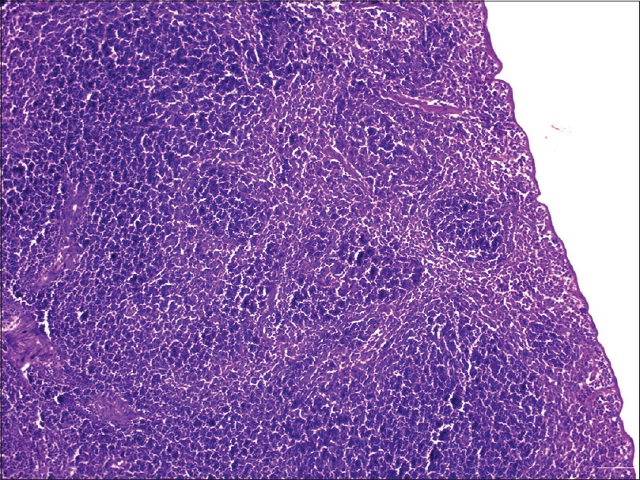

Immunomodulatory effect of Kaempferia parviflora against cyclophosphamide-induced immunosuppression in Swiss albino mice